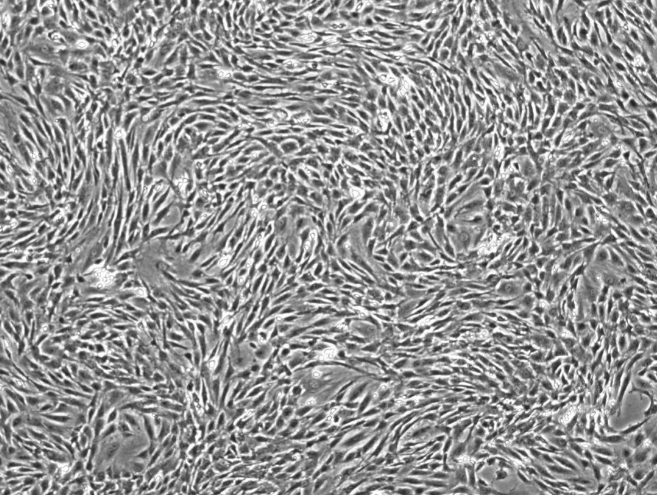

细胞传代到第 3 代时,生长融合后,细胞形态均一,呈长梭形集落样分布,并可重叠生长,细胞纯度可达 95%以上。此时细胞可用于后续实验,或采用表表面标志物进一步验证其纯度:验证标准为CD34 阴性,CD44 阳性。

从本实验结果中可见:全骨髓培养法可分离培养出纯度高、活力旺盛的骨髓间充质干细胞。